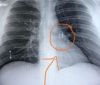

Piercing perdido há cinco anos é encontrado em pulmão de homem